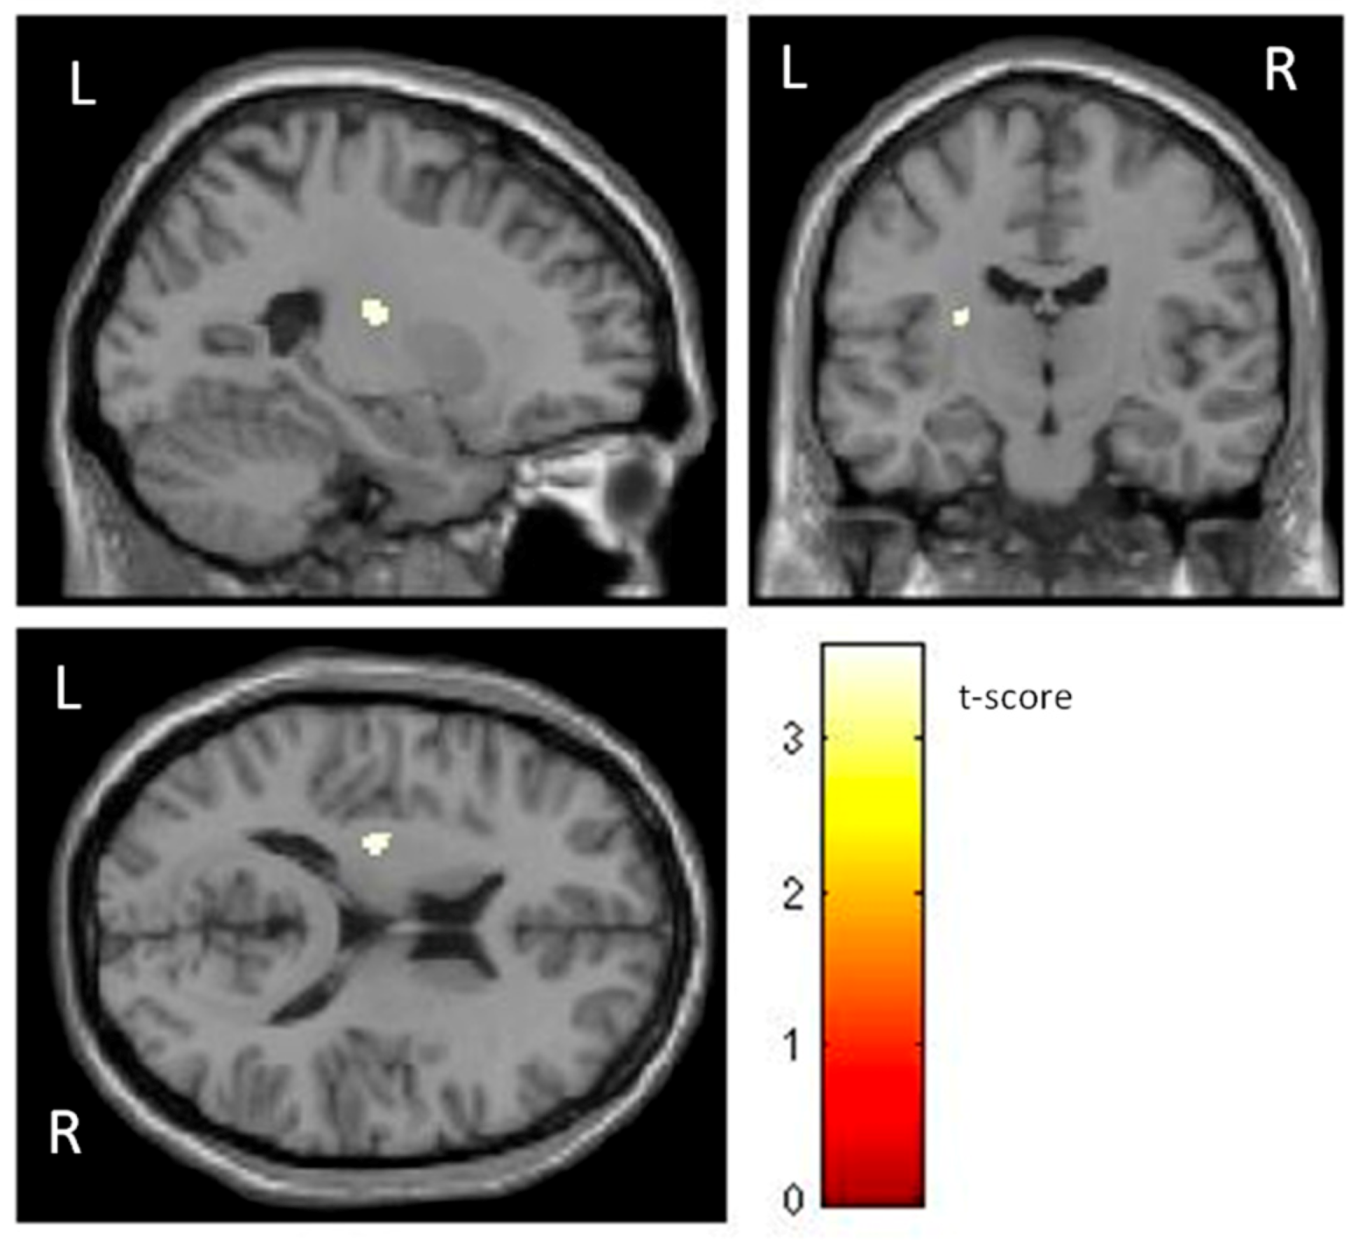

Additionally, individuals with phobia showed a larger GMV in the left putamen than non-fearful controls (t (60) = 3.48, p < 0.001) (Table 1 and Figure 2), with a moderate effect size. The putamen is related to complex motor regulation and the facilitation of different types of learning.

Figure 2. Significant differences in GMV of the putamen between individuals with phobia (larger) and non-fearful controls (corrected with Gaussian random field theory with a significance threshold of a voxel-wise value of p < 0.001 and cluster probability of p < 0.05). T-score is represented on a color bar.